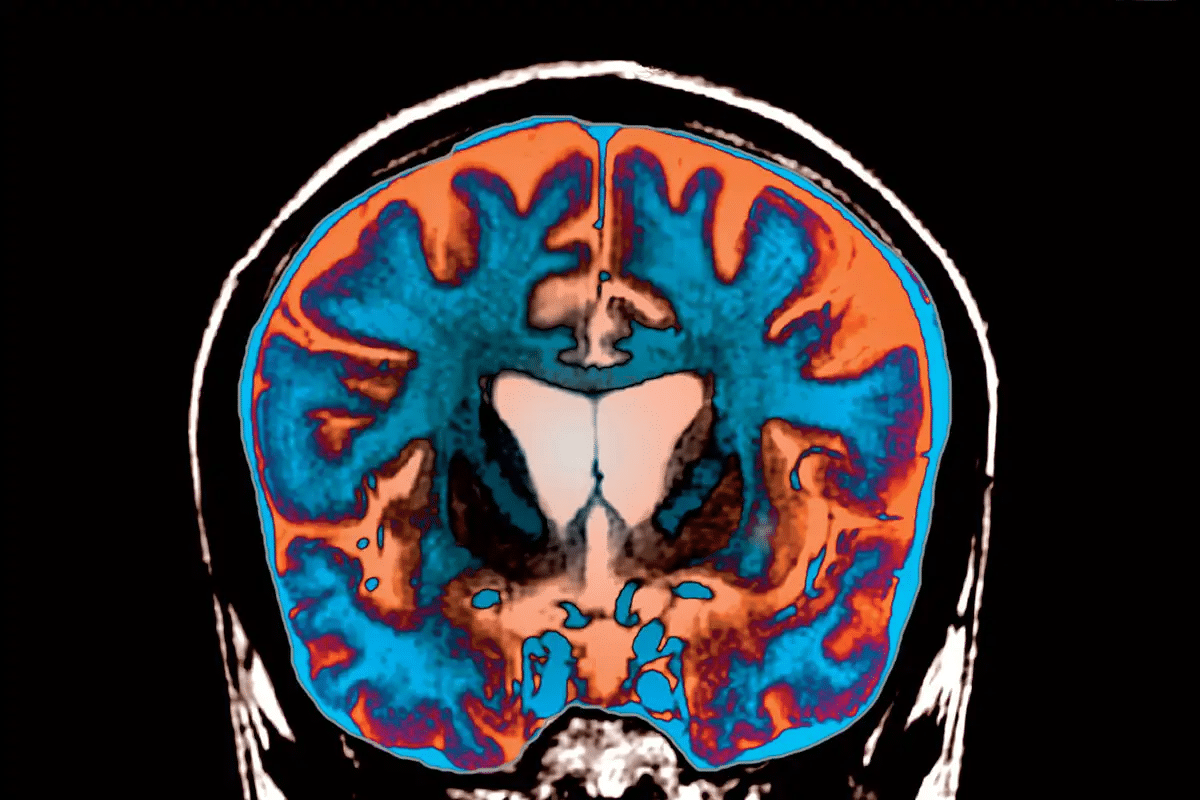

The Brain Changes in Frontotemporal Dementia

Frontotemporal dementia changes the brain in key ways. It mainly affects the frontal and temporal areas. These changes cause neurons to shrink or die.

Affected Brain Regions: Frontal and Temporal Lobes

The frontal lobe is key for making decisions and solving problems. It also controls our behavior. The temporal lobe is important for language and memory.

Damage to these areas leads to FTD symptoms. These include changes in personality, trouble with language, and motor issues.

Neurological Damage Patterns

FTD has specific damage patterns. It causes neuronal loss and gliosis. This means glial cells grow in response to neuron damage.

This damage follows patterns that match the symptoms patients show. For example, frontal lobe damage affects behavior. Temporal lobe issues lead to language and memory problems.